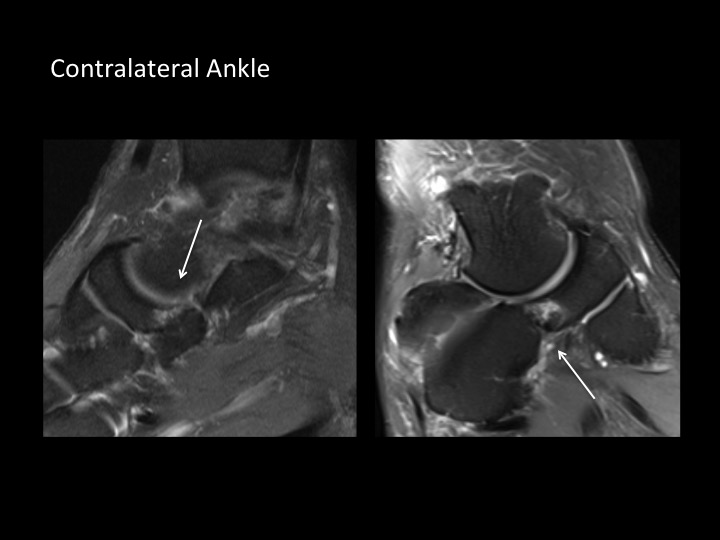

Although there have only been 9 cases of navicular-cuboid coalition reported up to 2012 (up to and including the reference for case #1390), here is another case in a 30M with bilateral non-osseous navicular-cuboid coalition (white arrows; changes more pronounced on the left). He has left-sided Haglunds deformity, which relates to his symptoms. Although the 4 cases reported in the reference from #1390 had midfoot pain, I am struck that this patient, and the 10 yr old from #1390 both present with hindfoot pain. I imagine the midfoot tarsal coalition might have a global impact on foot biomechanics.

navicular-cuboid coalition